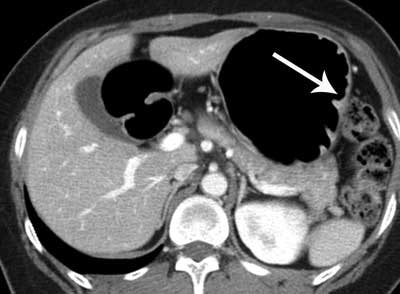

Above: Axial CT image shows questionable thickening and enhancement of inner mucosal layer (arrow). Bottom left: Virtual gastroscopic image clearly shows ulcerative lesion with abrupt termination of folds at the same location as axial CT image. Bottom right: Conventional gastroscopic image reveals a malignant ulcer with abrupt termination of gastric folds. This lesion was diagnosed as early gastric cancer on biopsy. Images courtesy of Dr. Jin Woong Kim and Dr. Sang Soo Shin.The degree of gastric distension was considered to be adequate when the gastric lumen was distended greater than 50% of the expected maximal luminal distension. Single-phase (portal venous phase) contrast-enhanced CT was performed after intravenous injection of 100 to 150 mL of iodinated contrast material with a power injector (Empowered CTA, E-Z-EM) at a rate of 3 mL/sec through an antecubital vein. The total amount of injected contrast material was adjusted according to the body weight of the patients (2 mL/kg).

Overall, gastric cancer was identified in 123 (96.9%) of the 127 cancers on the CT images. Four undetectable cancers on CT were pathologically staged as T1a (n = 3) and T1b (n = 1), respectively. In cases of early gastric cancer (EGC), 56 (73.7%) of the 76 cancers were visible on both the 2D and the 3D images, whereas EGC was identified only on the 2D and the 3D images in two (2.6%) and 14 (18.4%) cancers, respectively.

"All the AGCs [advanced gastric cancers] were visualized on both the 2D and the 3D images. With respect to the pattern of the gastric mural layering at the site of the gastric cancer and the adjacent normal gastric wall, among 109 gastric cancers that were detected on the 2D images, five (4.6%) and 104 (95.4%) cases were classified as single-layered and multilayered, respectively," the authors wrote.

Most patients (95.4%) showed a multilayered structure of the gastric wall around the lesion site. This observation may be because the gastric wall infiltrated by the tumor becomes thickened and/or stiff, which may negatively affect the distensibility at the site of the gastric cancer and the adjacent normal gastric wall. Alternatively, tumoral infiltration into the gastric wall may be accompanied by inflammatory or edematous change beneath the cancer, which may result in the exaggeration of the multilayered structure of the gastric wall.